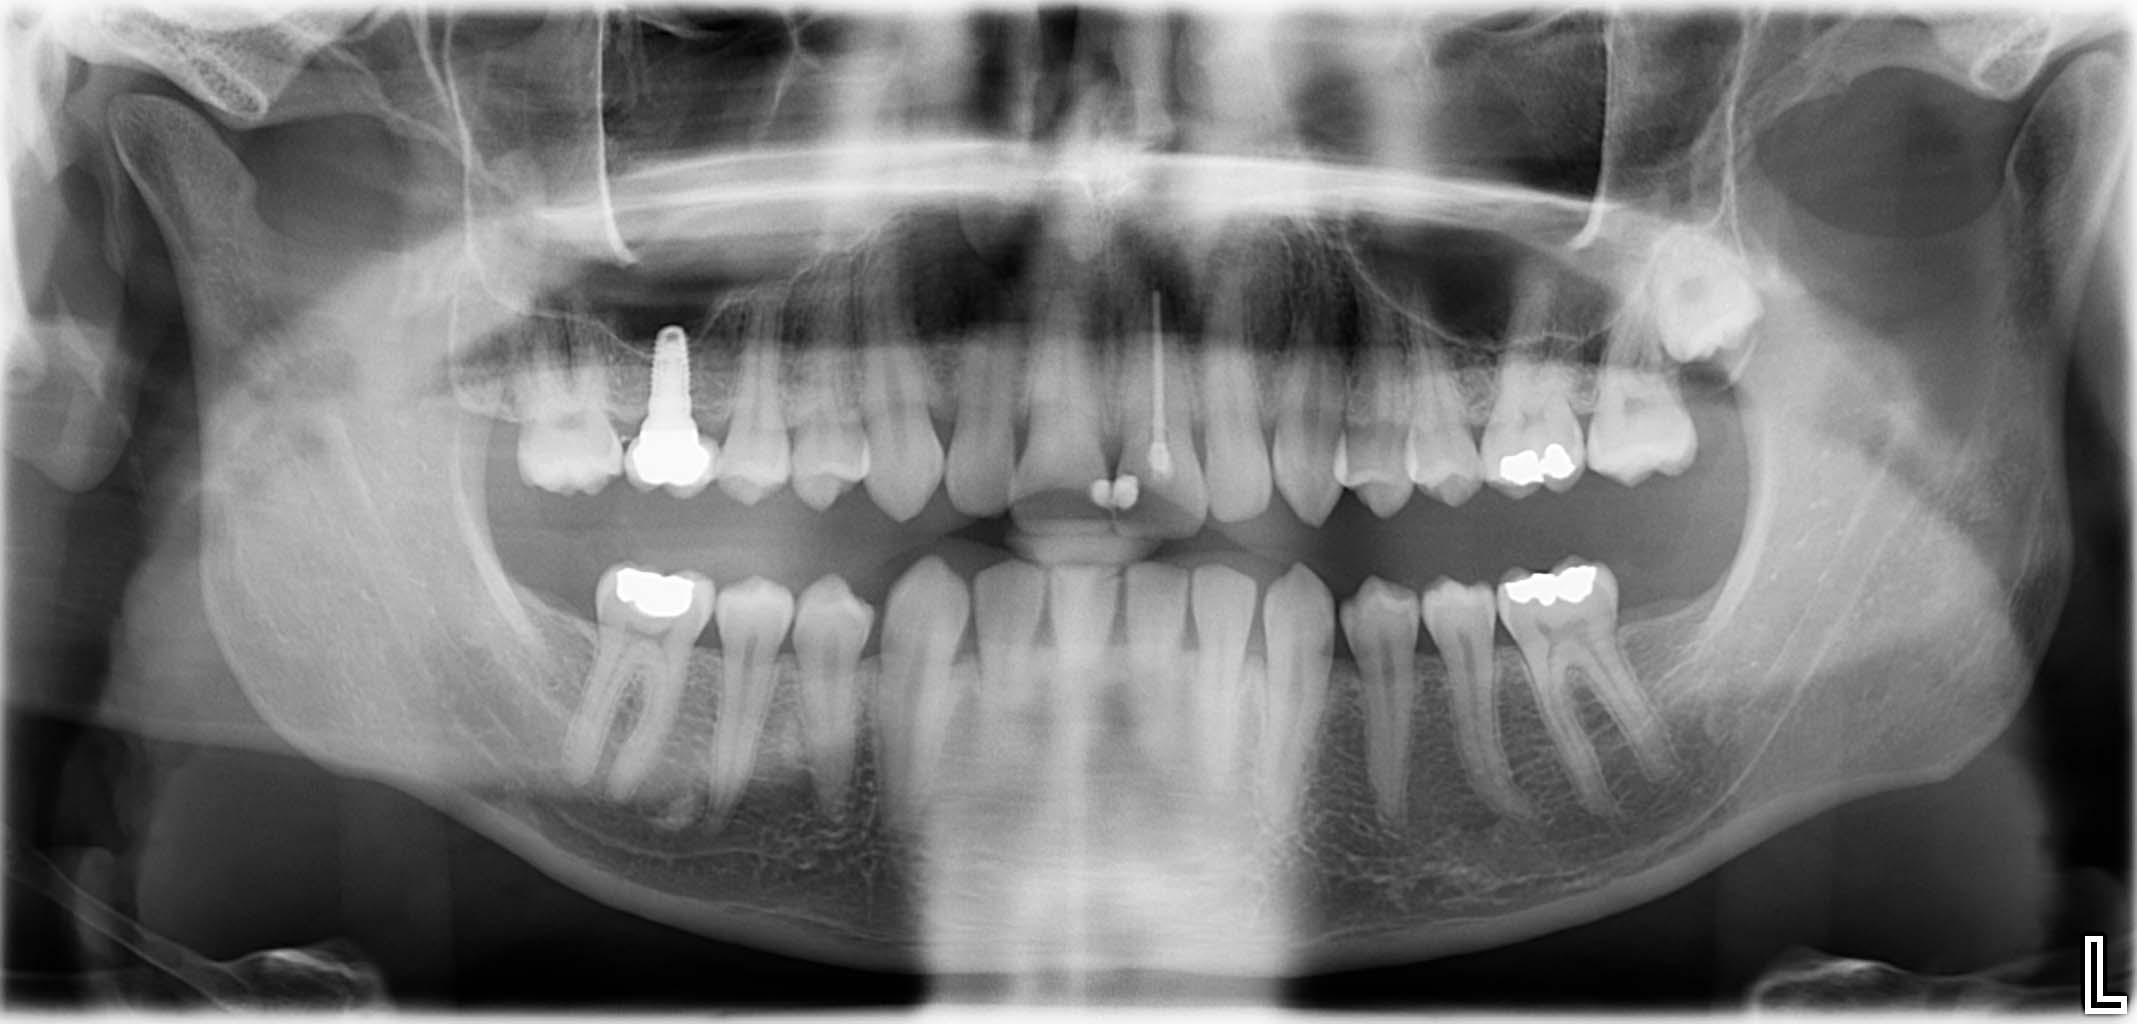

Erfolgreich implantierte Patientenfälle (klinische Fotos)